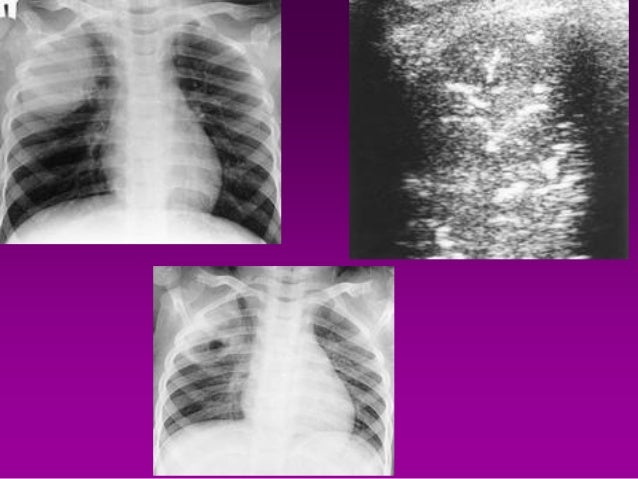

Corona Virus Infection

Corona Virus Chest X Ray

Wuhan Coronavirus X Ray

Wuhan Coronavirus Cxr